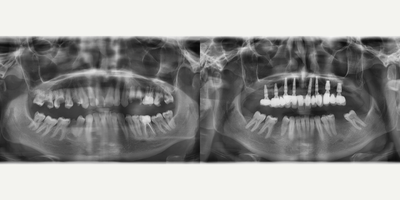

45-54 year old woman treated with All-on-4 Dental Implants, Dental Implants

Our patient had an old mobile bridge in upper jaw and the teeth underneath were hopeless. We performed exttaction of.the teeth which have bone loss and performed All-on-4 implant treatment for upper jaw to avoid a prolonged treatment such as sinus lifting and bone grafting.Lower jaw has been treated by standard implant treatment with 6 implants.